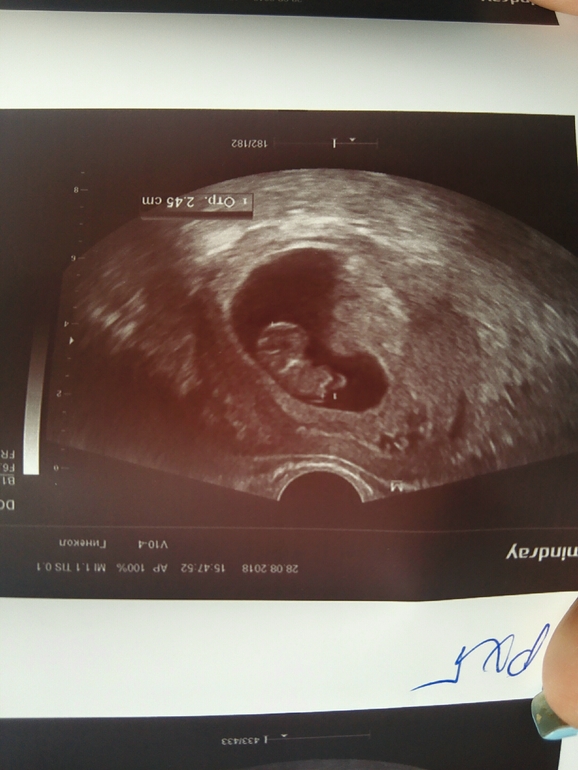

Девочки кто пил транексам при ретрохориальной гематоме? Если выделений вообще не было? У меня вчера было мало мало, узнали что гематома, прописали транексам, но его ведь пьют когда кровь идёт? А у меня не идёт ничего . Или это так надо? Что б рассосалась . Lika Костя 3 года 6 месяцев Тюмень 1533914 Комментарии Посмотреть комментарии

Да, при наличии ретрохориальных гематом кровянистые выделения могут иметь место . Поэтому в лечение обязательно должны быть включены: 1) гемостатики - Транексам (препарат первой линии терапии!) по 500мг х 3рд 2)Сохраняющая терапия - Дюфастон по 1т х 3рд 3) при наличии болевого синдрома - свечи с папаверином ректально по 1св 3-4 рд .

РЕТРОХОРИАЛЬНАЯ ГЕМАТОМА ПРИ БЕРЕМЕННОСТИ!!! . . . Сказала попить Дюфастон и Транексам, через 5 дней на УЗИ . У кого была подобная ситуация, чем лечили, . . .